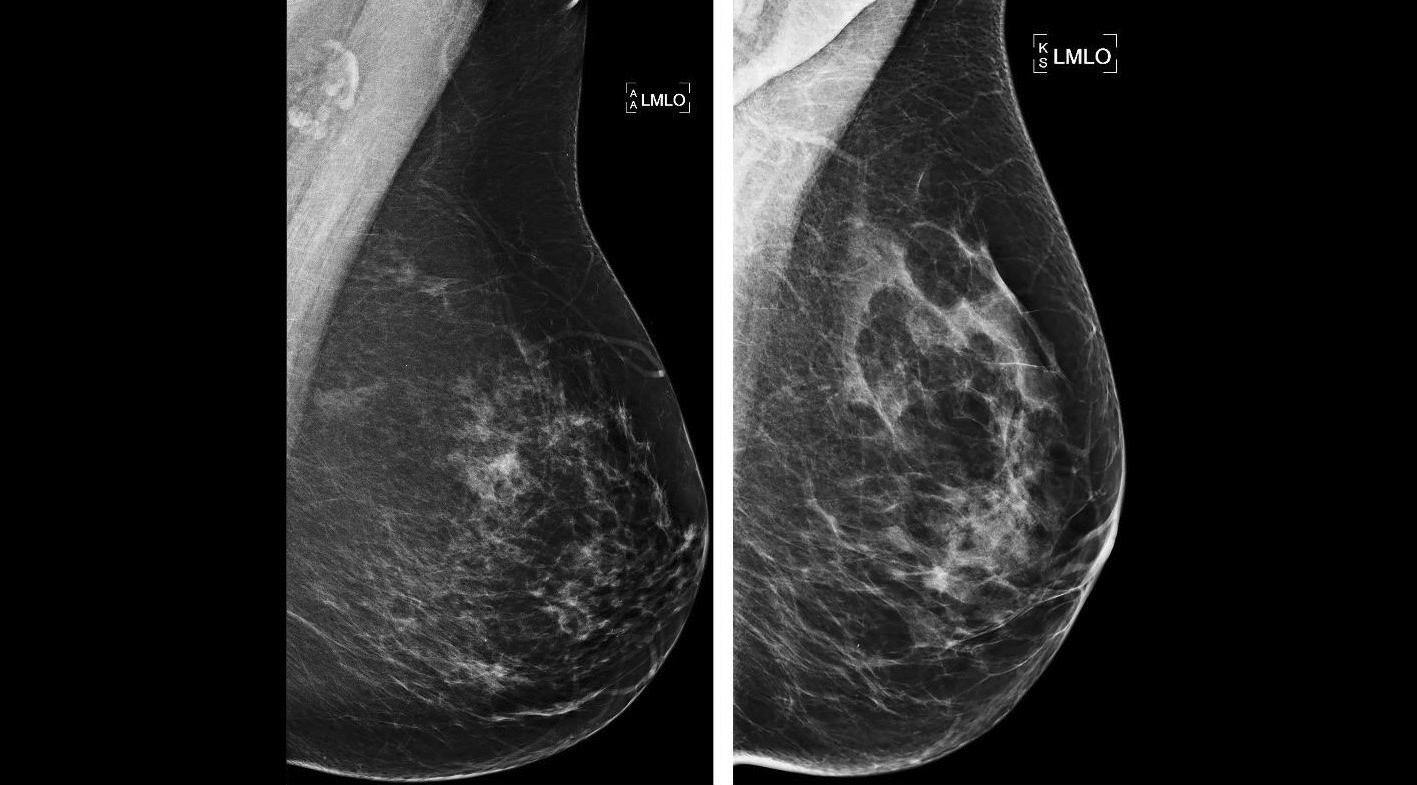

Sur la dématérialisation de la seconde lecture des mammographies de dépistage, l’Allier est l’un des territoires qui a sauté le pas. Depuis 2018, la dématérialisation a été mise en place dans ce département rural, intégré à la région Auvergne-Rhône-Alpes (AURA). Aujourd’hui, environ 75 % des mammographies y sont dématérialisées en seconde lecture.

Avec l’Auvergne, le département de l’Allier fut l’un des premiers territoires en France à implémenter ce dispositif du fait de son organisation et de sa physionomie un peu particulière : « Historiquement, la seconde lecture sur négatoscope s’organisait sur huit sites du CRCDC, et seul le site de l’Allier dérogeait à cette règle, explique Pierre Darbelet, responsable du site et de la dématérialisation en région AURA. Notre département est un territoire rural avec trois villes de taille égale espacées d’une heure de route, à savoir Vichy, Moulins et Montluçon. Dans les années 90, il avait été décidé de décentraliser la sec